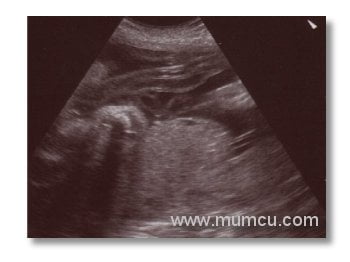

16 haftalık gebelik biparietal çap (BPD)ı

Abdominal ultrasonografi